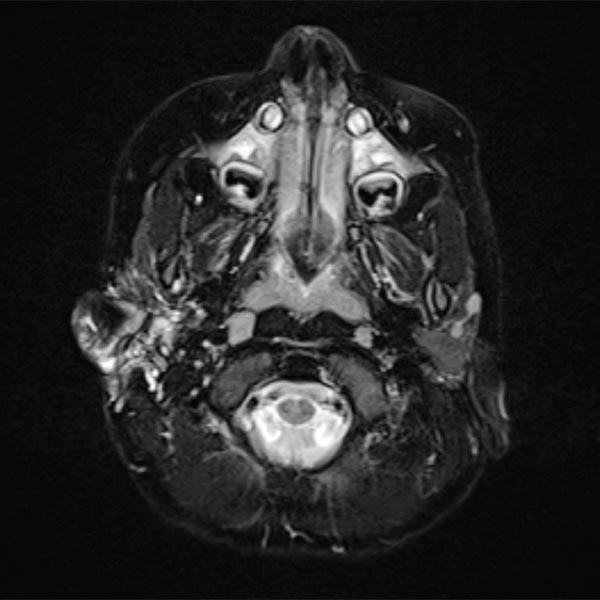

Gemischt makro- und mikrozystische LM im Bereich der Parotisloge rechts um das Ohr herum ziehend in einer T2-gewichteten, fettgesättigten transversalen MRT-Schicht.